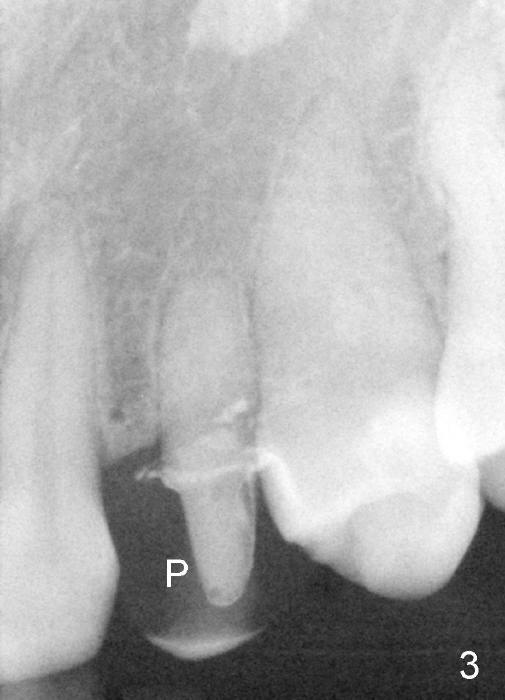

The upper left deciduous canine of a lady in her early forties looks functional 9 and 5 years ago (Fig.1,2). She wanted to close the diastema mesial to the deciduous tooth (Fig.2 *). The tooth was prepared for a provisional (Fig.3 P) and definitive restoration (Fig.4 C). The tooth becomes mobile 4 years post cementation (Fig.5).